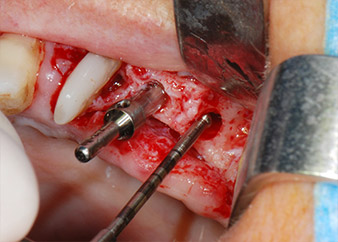

En el siguiente paso, los lechos del implante se prepararon en las posiciones 25 y 26 con instrumentos rotatorios, utilizando un contra-ángulo con un coeficiente de transmisión de 20:1 (WS-75 L, W&H), junto con el nuevo potente motor de implantes Implantmed de W&H (figuras 8 y 19).

A continuación, los implantes (Restore, Keystone Dental, 3,75 mm de diámetro, 8,0 mm de longitud) se colocaron con el motor de implantes (figuras 11 y 12).